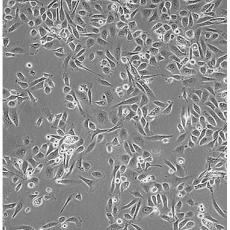

PC-3(PC 3)

中文名稱 人前列腺癌細(xì)胞

組織來源 前列腺癌;骨髓轉(zhuǎn)移;男性

生長特性 adherent

形態(tài)特征 epithelial

細(xì)胞描述 PC-3源于一位62歲白人男性IV級前列腺腺癌患者的骨轉(zhuǎn)移灶;有低水平的酸性磷酸酶活性和5-α-睪酮還原酶活性。